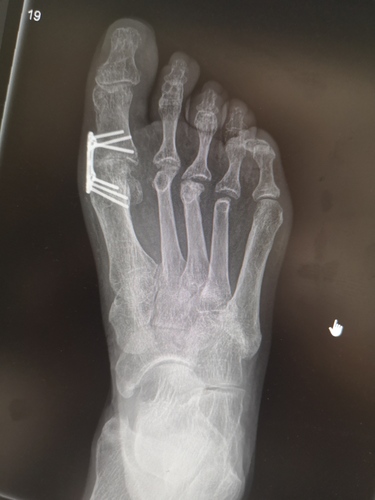

Specjaliści z II Kliniki Ortopedii i Traumatologii Narządu Ruchu GUMed dr Leszek Kuik i kierownik jednostki dr hab. Piotr Łuczkiewicz wraz z naukowcami z Katedry Wytrzymałości Materiałów Wydziału Inżynierii Lądowej i Środowiska Politechniki Gdańskiej opracowali nową metodę stabilizacji w usztywnieniu pierwszego stawu śródstopno-paliczkowego (MTP-1), wykorzystując stabilizację płytką przyśrodkową.

– Zabieg usztywnienia jest powszechnie stosowanym sposobem leczenia zaawansowanych zmian zwyrodnieniowych stawu MTP-1. Niestety wyniki leczenia, zwłaszcza chorych z reumatoidalnym zapaleniem stawów, znaczną osteoporozą oraz przy zabiegach rewizyjnych, nadal są niezadowalające u istotnego odsetka pacjentów. Nowo opracowana technika operacyjna została przetestowana na modelu matematycznym w metodzie elementów skończonych, stworzonym wspólnie z naukowcami z PG. Eksperymenty jednoznacznie wykazały lepsze właściwości biomechaniczne płytki przyśrodkowej w porównaniu do dotąd powszechnie stosowanej płytki grzbietowej – tłumaczył dr Leszek Kuik z II Kliniki Ortopedii i Traumatologii Narządu Ruchu GUMed.

W związku z obiecującymi wynikami przeprowadzono badanie pilotażowe, stosując płytkę przyśrodkową u 20 pacjentów ze zwyrodnieniami stawu MTP-1. Wyniki funkcjonalne oceniono po ponad roku od zabiegu.

– Otrzymane wyniki potwierdziły dużą skuteczność i bezpieczeństwo nowej metody. Technika z użyciem płytki przyśrodkowej została wprowadzona na stałe do sposobów leczenia Kliniki. Wciąż trwają badania nad ulepszeniami modelu matematycznego, jak i techniki operacyjnej – wyjaśnił dr Leszek Kuik.